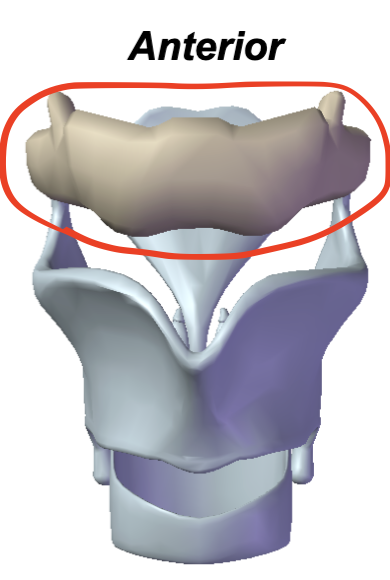

Hyoid bone

Where are the parts of the hyoid bone from top to bottom?

Greater cornu, Lesser cornu, Corpus